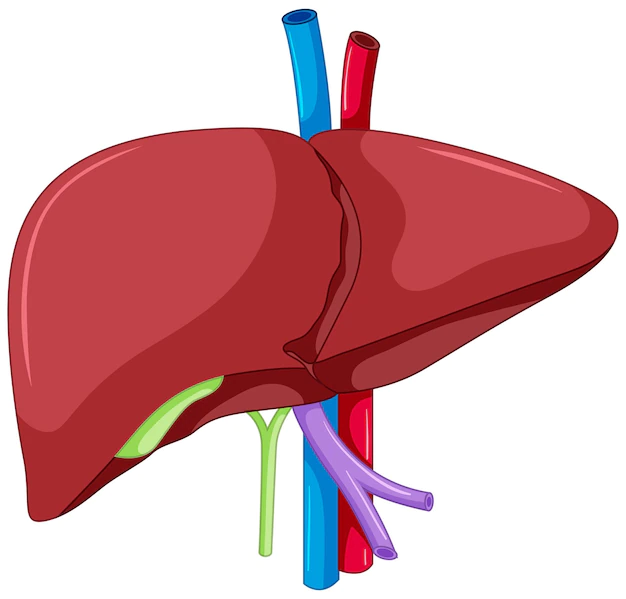

Es el órgano más voluminoso del organismo. Está situado debajo del diafragma, por encima del duodeno y por delante del estómago. La sangre llega al hígado por dos vías:

- la de la arteria hepática

- la de la vena porta hepática.

El drenaje venoso del hígado se realiza por las venas hepáticas, voluminosos afluentes de la vena cava inferior.